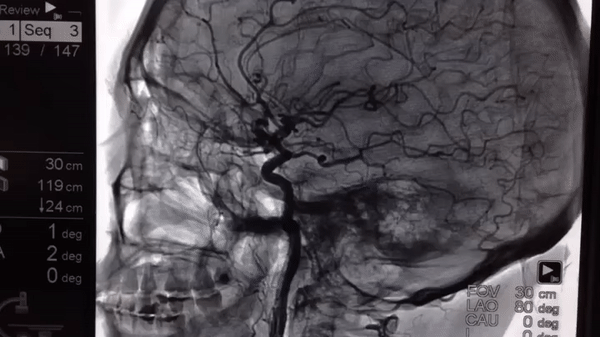

9. Check out all the arteries that run through our brains

Illustration de l'article : 14 X-ray images that reveal a hidden story

© Ryabkov / Pikabu